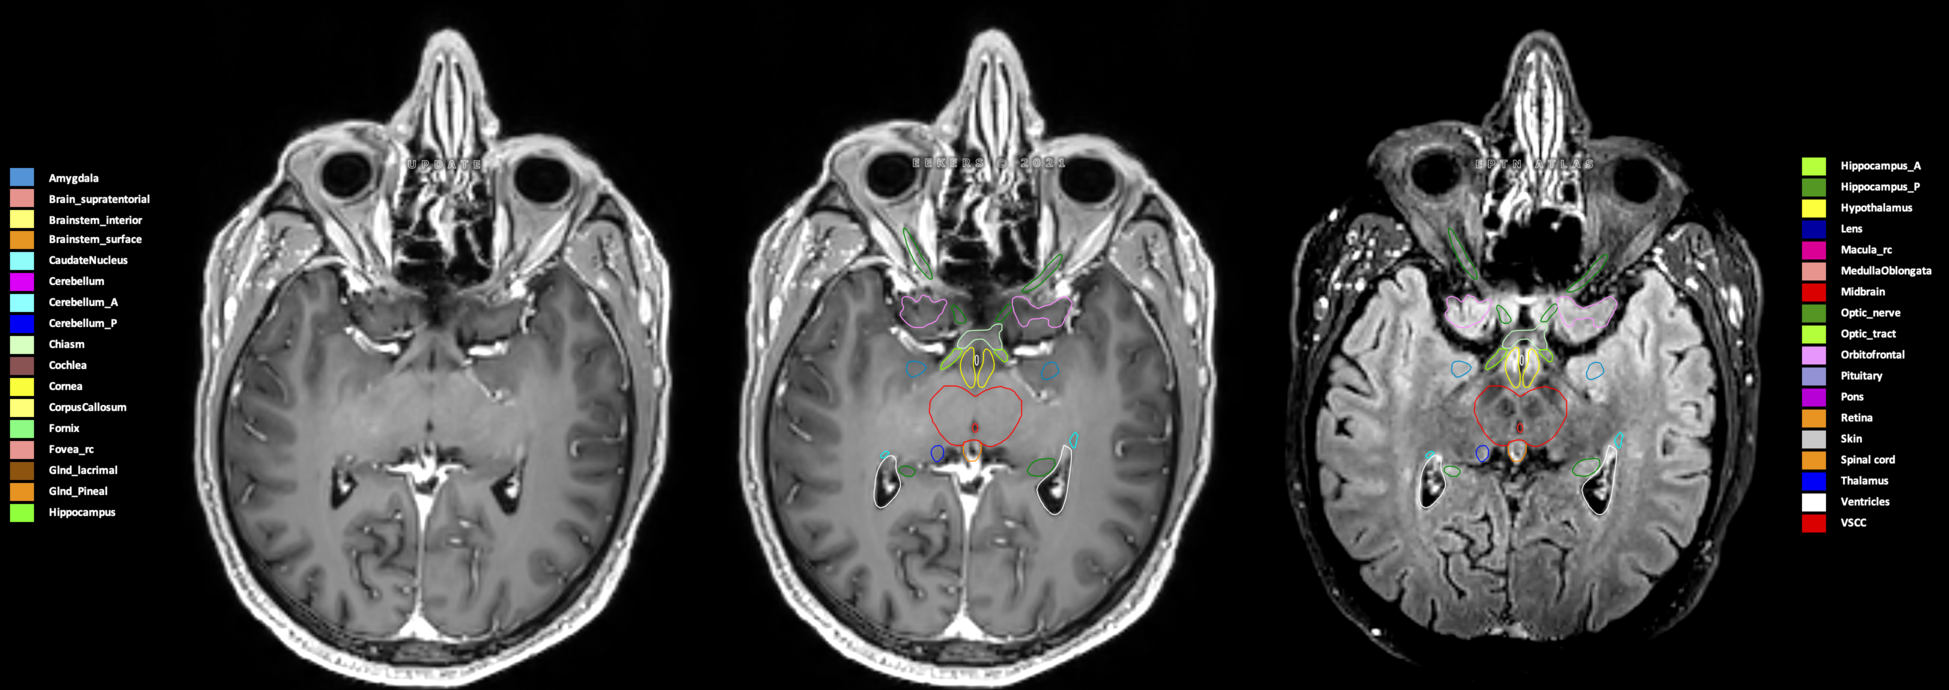

Eekers et al. have published an international neurological atlas for contouring of organs at risk in consensus with the European Particle Therapy Network (EPTN) in 2018 and an update in 2021. The purpose of this consensus atlas is to decrease inter- and intra-observer variability in delineating OARs relevant for neuro-oncology.

Included are all OARs known to be relevant for radiation-induced toxicity in neuro-oncology: brain, brainstem (midbrain, pons, medulla oblongata), chiasm, cerebellum (anterior & posterior), cochlea, cornea, hippocampus (anterior & posterior), hypothalamus, lens, lacrimal gland, optic nerve, pituitary, skin, and vestibular & semicircular canals. To further facilitate research on cognition, vision and radiological changes after irradiation of the brain, potential clinically-relevant OARs are included: amygdala, caudate nucleus, cerebellum (anterior & posterior), corpus callosum, fornix, macula, optic tract, orbitofrontal cortex, periventricular space (PVS), pineal gland, and thalamus.

Three-dimensional delineation of the 25 consensus OARs for neuro-oncology are shown on CT (WW/WL 120/40, 3000/600), 3T MR images, (T1Gd, T2FLAIR 1mm) and 7T MR (MP2RAGE 0.7 mm). All are presented in transversal, sagittal and coronal view.